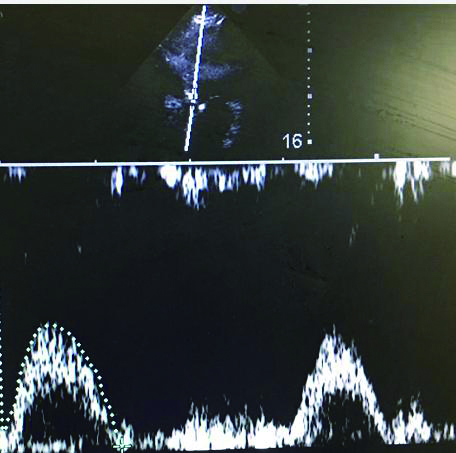

充分暴露前胸部,于胸骨旁长轴切面,选取主动脉瓣根部测量左室流出道直径与截面积。选取心尖五腔心切面,通过脉冲多普勒测量动脉流速,计算左心室流出道收缩高峰期的流速时间指数,测量心率,最后通过心脏检查软件包自动计算出CO(图 3、4)。通过上述PLR试验,联合超声获得的CO,最后计算ΔCO值,ΔCO≥15%定义为容量反应性阳性;反之为容量反应性阴性。

| 图 4 心尖部五腔心流速时间指数测量 Figure 4 The measurement of apical velocity time index at five-cavity flow |